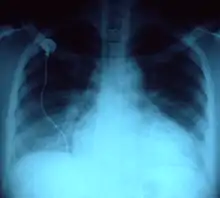

При клінічному варіанті гострої серцевої недостатності по типу лівошлуночкової недостатності у хворих з'являються скарги на задишку, спочатку помірну, а при важких формах із приєднанням кашлю, часто з виділенням пінистого мокротиння, при огляді хворого спостерігаються блідість або ціаноз шкіри, яка одночасно волога або липка на дотик, артеріальний тиск у хворого нормальний або дещо підвищений, при аускультації легень вислуховуються вологі хрипи над усією поверхнею легень, а на рентгенографії органів грудної клітки спостерігаються явища застою в легенях.

При гострій серцевій недостатності пацієнти потребують екстрених діагностичних і лікувальних заходів, тому в діагностиці гострої серцевої недостатності важливішу роль грають анамнез захворювання, клінічна симптоматика та дані огляду хворого та його фізикальне обстеження. З інструментальних методів обстеження в діагностиці гострої серцевої недостатності найважливіше місце посідають ЕКГ, яке дає можливість побачити ознаки гострого коронарного синдрому, порушення ритму або провідності, ознаки перевантаження або гіпертрофії камер серця, а також перикардиту; ехокардіографія дає можливість оцінити систолічну і діастолічну функцію лівого і правого шлуночка, стан і функцію клапанів серця, ознаки захворювань перикарду, місце ймовірного пошкодження міокарду при інфаркті міокарду; рентгенографія грудної клітки проводиться для оцінки розмірів та контурів серцевої тіні, а також діагностики застою в легенях та інфекційних захворювань дихальної системи (пневмонії, плеврити, хронічні обструктивні захворювання легень); коронарографія при гострому коронарному синдромі дає можливість оцінити стан коронарних артерій для визначення потреби у проведенні реваскуляризацій них процедур.[10]

У діагностиці хронічної серцевої недостатності важливу роль також мають анамнез захворювання, клінічна симптоматика та дані огляду хворого та його фізикального обстеження. Із інструментальних методів обстеження найважливіше місце посідають ЕКГ, на якому можна виявити ознаки гіпертрофії і перевантаження камер серця, рубцеві зміни після перенесеного інфаркту міокарду, аритмії (зокрема фібриляцію передсердь), за необхідності хворим може проводитись холтерівське моніторування; при рентгенографії грудної клітки визначаються збільшення розмірів серця та венозний застій у нижніх відділах легень; ехокардіографія дає можливість визначити наявність і характер дисфункції лівого шлуночка, стан клапанів серця, розміри порожнин серця, стан ендокарду та перикарду, виявити наявність тромбів у порожнинах серця; коронарографія дає можливість провести диференційну діагностику ішемічної і некоронарогенної кардіоміопатії. З лабораторних методів обстеження для підтвердження діагнозу серцевої недостатності застосовується визначення передсердного натрійуретичного пептиду.[5][7]